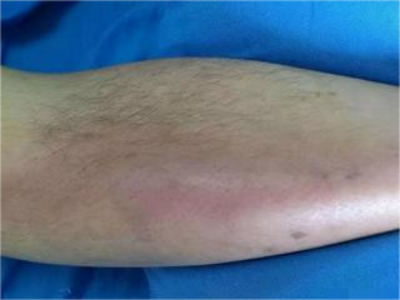

下肢深静脉血栓形成,可表现为肢体疼痛、肿胀、股青肿等,具体如下:

2、肢体肿胀:肿胀通常局限于小腿或发生全肢肿胀;

3、皮肤改变:肢体可发绀,皮温升高,浅静脉扩张;